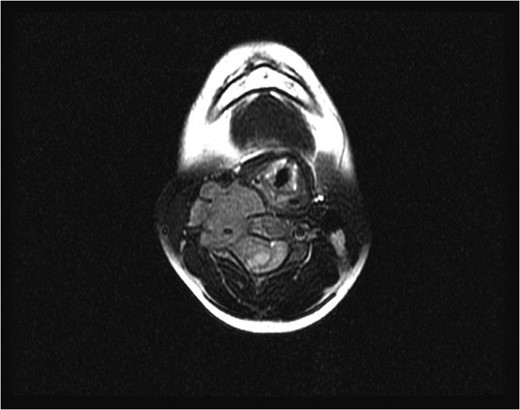

Sagittal magnetic resonance image 3 years after the second surgery, showing small soft tissue enhancement, suggesting a possible residual tumor, which remained unchanged with follow-up.